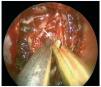

Caso clínico: Varón de 42 años de edad con paresia del VI par craneal derecho y estudios de imagen mediante resonancia magnética y tomografía computarizada craneales sugestivos de displasia fibrosa esfenoclival. Se lleva a cabo un abordaje endonasal expandido transpterigoideo completamente endoscópico, obteniéndose una amplia descompresión de las estructuras vasculonerviosas de la base del cráneo. Durante el procedimiento se utiliza neuronavegación y el canal vidiano como referencia anatómica fundamental de la carótida en su segmento lacerum.

Case report: A 42-year-old male with right sixth cranial nerve palsy. Cranial MRI and CT showed a central skull base lesion with diagnostic suspicion of FD. Patient underwent a full endoscopic transpterygoid EEA, achieving a wide skull base neurovascular decompression. Neuronavigation and the vidian canal landmark resulted mandatory during intraoperative procedure.

Discusión: El AEE transterigoideo es una técnica segura y con amplio sustento en la literatura científica. En manos adecuadas, podría reducir la morbilidad asociada a los abordajes transcraneales clásicos, ya que permite un máximo potencial resectivo sobre las lesiones a tratar, con una mínima distorsión sobre las estructuras craneofaciales circundantes. Para su realización se utilizan referencias anatómicas claves como el agujero y canal del nervio vidiano. La indicación de tratamiento quirúrgico en los casos de DF de base craneal ha de establecerse en función de la presencia de sintomatología.

Discussion: The transpterygoid EEA is a safe technique consistently supported in the literature. It may reduce the morbidity associated to the classic transcranial approaches, since it permits maximum resection with minimum craniofacial distortion. The vidian hole and canal are the landmarks used to locate and avoid injury to the lacerum segment of the carotid injury. The surgical treatment indication in FD cases must be established in symptomatic patients.